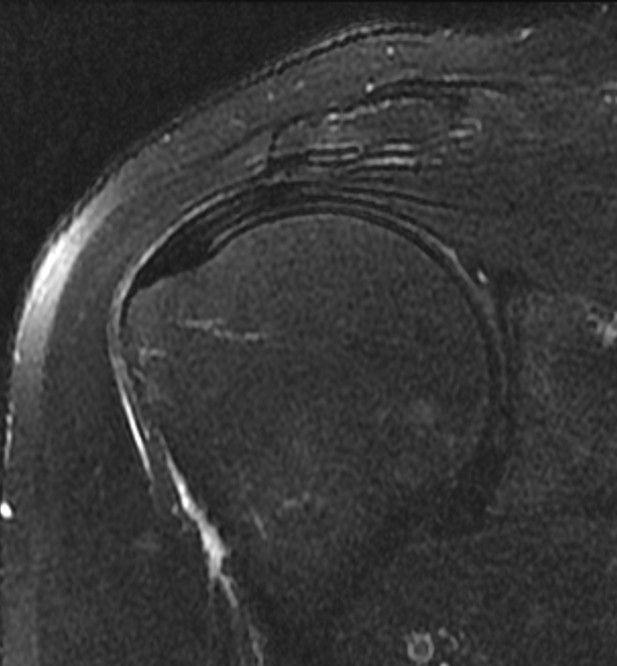

수개월간 지속되던 우측 어깨통증으로 꾸준한 보존적 치료(약물,주사,충격파,도수재활치료 등)을 시행하였으나 증상이 호전되지 않고, 점차 팔을 옆으로 들때나 뻗을때 통증이 심해지고, 팔을 옆으로 들어 밖으로 돌릴때 더 통증이 심해지는 양상. 방문한 병원에서는 석회가 조금 있고, 회전근개주위 염증이 있으며, 뼈가 자라서 힘줄을 손상시킨다는 진단을 받음. 이후로 재생주사,스테로이드 주사치료도 병행하였으나 증상이 호전되지 않고, 움직일때마다 통증때문에 팔에 힘을 주기가 어려워짐. 시술전(pre) MRI검사상 회전근개 위쪽(점액낭쪽)으로 힘줄염과 회전근개 일부가 벗겨진 부분손상이 확인되어 더핌스 축소봉합술을 시행함. 시술후(post) 시행한 MRI상 손상되었던 힘줄이 회복되었음이 확인되었고, 시술후 바로 일상생활/직장생활로 복귀하였으며, 어깨를 움직일때마다 발생했던 통증이 사라짐.